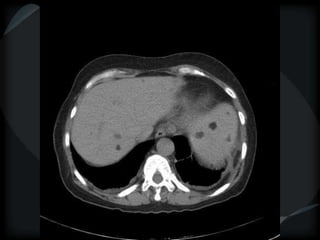

LAM

 Thin walled oval cysts

 Normal parenchyma

 Pleural effusion-chylous

 normal or hyperinflated lung

 angiomyolipoma